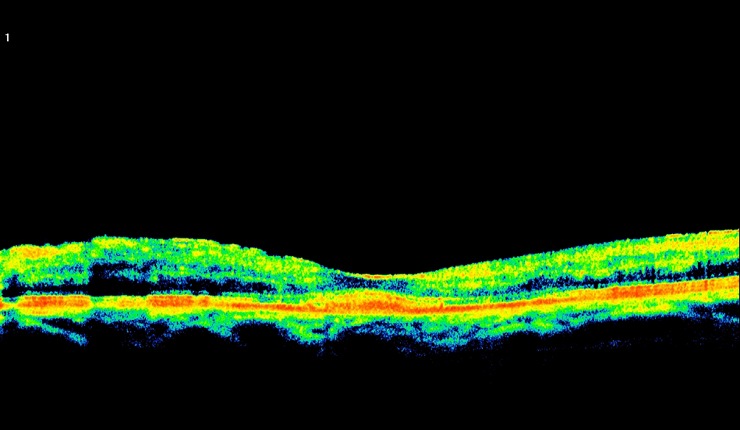

Highly reflective choroidal neovascular membrane (CNV) associated with AMD. Some residual fluid remaining at the interface of the CNV and outer retina.